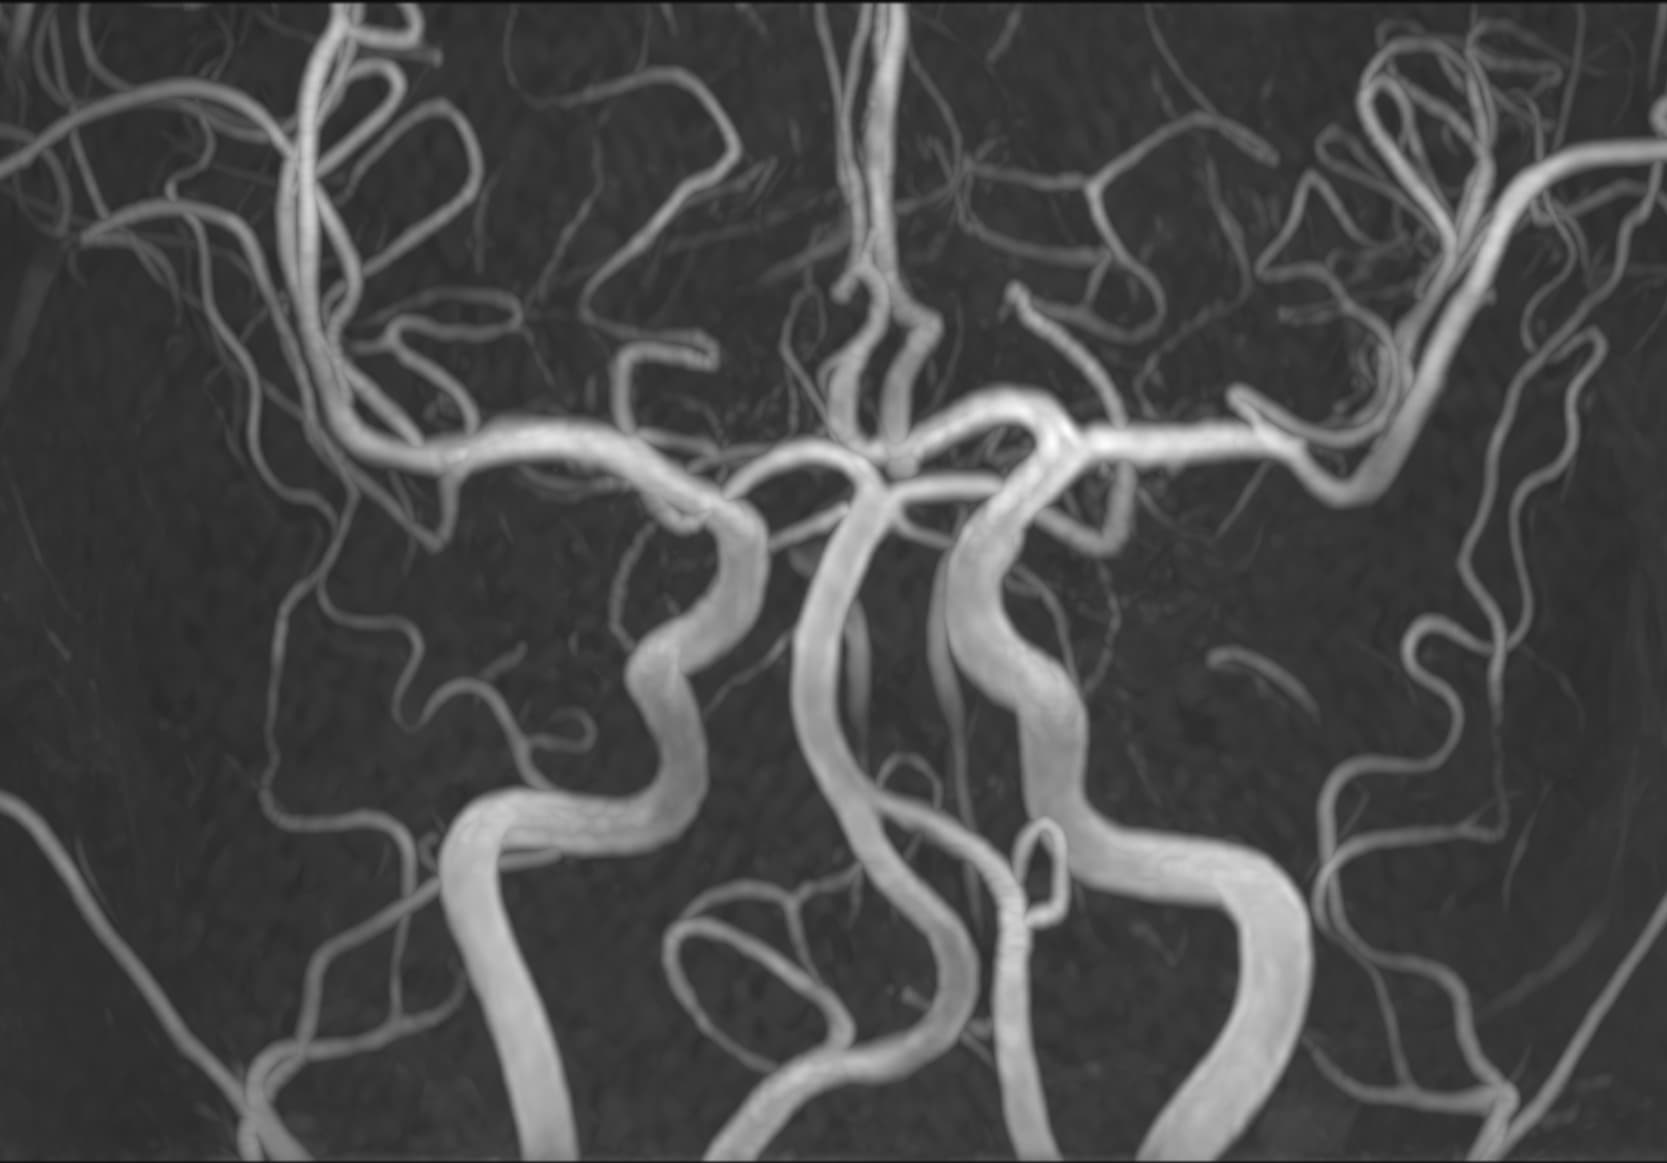

See real-world examples of SwiftMR™ across various MRI systems and anatomical regions

Scan time 03:14

Scan time 02:07

Scan time 03:08

Scan time 1:12

Scan time 04:53

Scan time 1:46